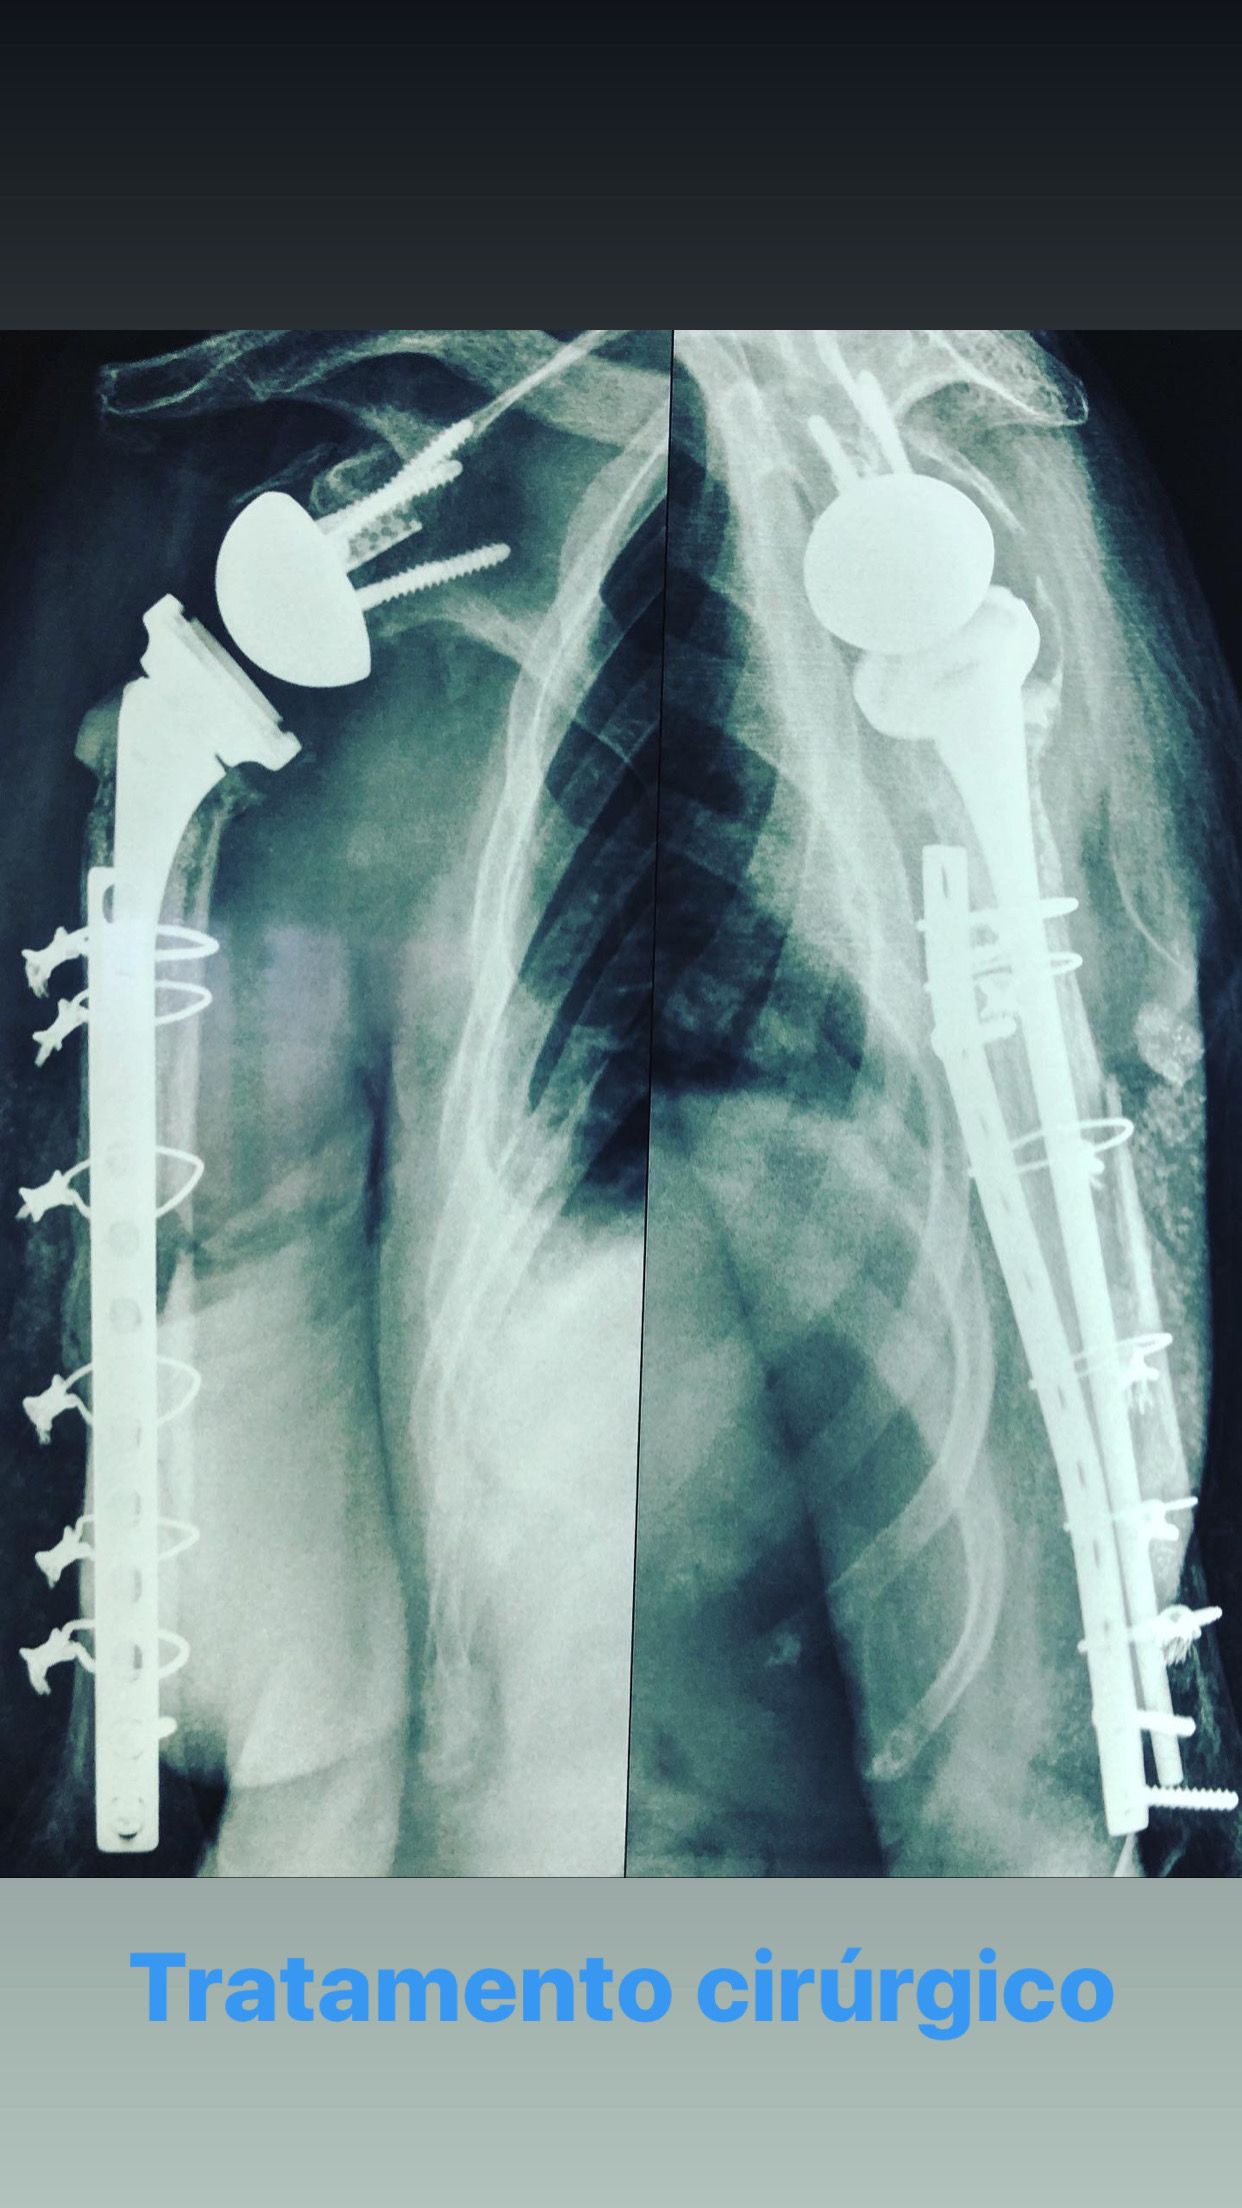

•Grande experiência em artroplastias(próteses) primárias e de revisão de joelho e ombro;

Tratamento cirúrgico de entesopatia ao nivel do joelho

Tratamento Cirurgico De Luxacao Ou Fratura Luxacao De Joelho

Tratamento Cirurgico De Lesao Aguda Capsulo Ligamentar Ao Nivel Joelho